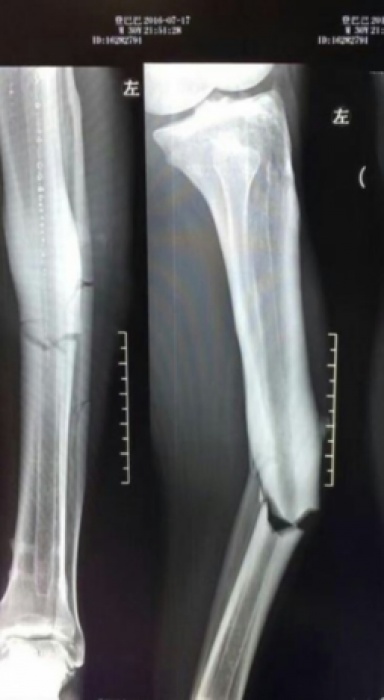

Demba Ba - cựu tiền đạo của Chelsea đã gặp phải một chấn thương kinh hoàng khi thi đấu tại Trung Quốc. Trận đấu diễn ra ngày 17/7, chân của Demba Ba gần như gãy làm đôi sau pha va chạm.

Nhìn vào tấm hình phim X-ray chụp vết thương của cầu thủ 31 tuổi sẽ khiến không ít người rợn xương sống. Ông quyển của Demba Ba gần như gãy lìa trong tai nạn vừa qua.

Theo các chuyên gia về y tế, chấn thương này có thể kết thúc sự nghiệp của tiền đạo từng thi đấu tại Premier League.

Chủ tịch đội bóng chủ quản của Ba ông Gregorio Manzano khẳng định sẽ dành cho cầu thủ của mình sự chữa trị tốt nhất có thể. Chấn thương này sẽ cần đến ít nhất 8 tháng để lành lặn trở lại.